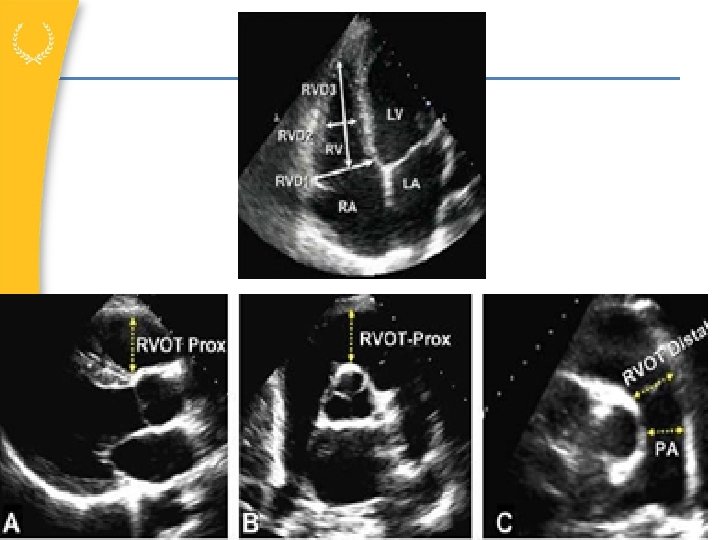

Measure the RV at end diastole from apical 4 chamber image demonstrating the maximum diameter of the RV without foreshortening

Right ventricle - size & function